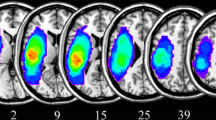

Aphasia types were classified based on the Western Aphasia Battery-Revised (WAB-R) (Kertesz 2007), which was administered by licensed speech-language pathologists (for full details of data fidelity and quality control, see (Spell et al. 2020)). Among the 96 participants included in the study sample, 39 were diagnosed with anomic aphasia, and 57 were diagnosed with Broca’s aphasia. Figure 1 shows a lesion overlap map of the participants in the two groups. Demographic statistics of the two groups are summarized in Table 1. The mean age in the anomic group was 62.73 y.o. (s.d. \(=11.97\); range \(=41\)) and the mean age in the Broca’s group is 59.82 y.o. (s.d. \(=10.35\); range \(=39\)). Respectively \(60\%\) and \(68\%\) of the participants in the anomic and Broca’s group were male. There was no significant difference in age and gender between the anomic and Broca’s group (age: p-value \(=0.42\) by two-sample t-test; gender: \(p =0.74\) by \(\chi ^2\)-test). All participants were in the chronic (>6 months) stage of stroke, where brain and behavior are more stable than in the initial months following stroke (acute stage) (Maas et al. 2012). For the anomic group, time post-stroke was a mean of 2.9 y (s.d. \(=3.42\); range \(=15\)) and for Broca’s was 4.3 y (s.d. \(=4.29\); range \(=16.5\)). This difference was not significant (\(p >.1\)). The mean WAB-R score for the anomic group was 85.74 (s.d. \(=6.38\); range \(=22.1\)) and 46.44 (s.d. \(=16.93\); range \(=59.1\)) for the Broca’s group. As shown in Fig. 2, the WAB-R score for the anomic group is significantly higher than the Broca’s group (p-value \(<0.01\) by two-sample t-test), since the participants with Broca’s aphasia tend to have a lower score in the section of fluency and repetition than the participants with anomic aphasia.